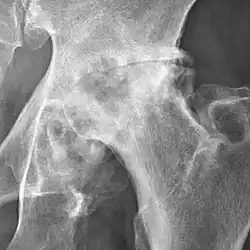

Hip

Hip joint with no signs of osteoarthritis.

The most commonly used radiographic classification system for osteoarthritis of the hip joint is the Kellgren–Lawrence system (or KL system).[6] It uses plain radiographs.